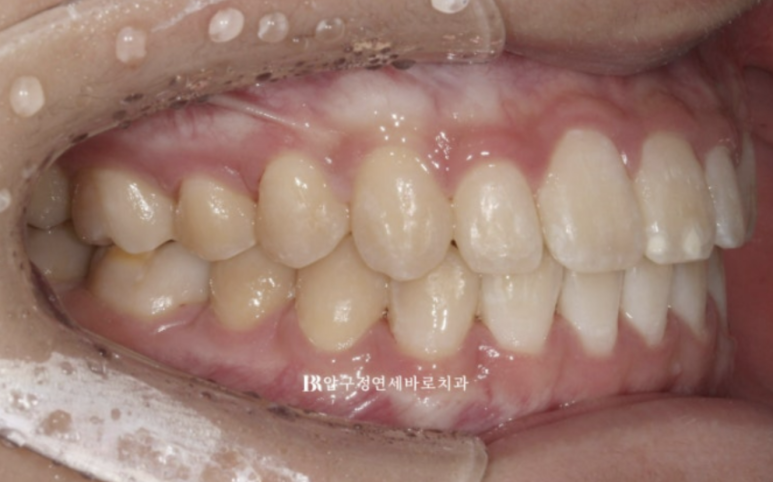

23.11

전체치료기간은 1년 1개월입니다.

앞니 각도가 정상으로 회복이 되면서

옥니 과개교합이 개선되면서

2022,07~23.11

뒤로 말려들어가 있던 입술에 입체감이 생기고 입매가 예뻐졌습니다.

교정으로 아래턱이 뒤로 들어간 것은 아니지만

입술 볼륨이 회복이 되면 주걱턱으로 보이던 것도 개선이 됩니다.

또 다른 치료 목표였던 앞니 노출도 개선으로 미소도 더 좋아졌습니다.